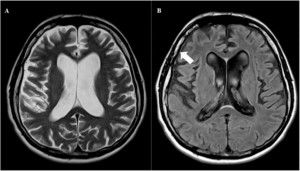

- Các phương pháp chẩn đoán hình ảnh như đo điện não đồ, chụp PET, chụp MRI,…